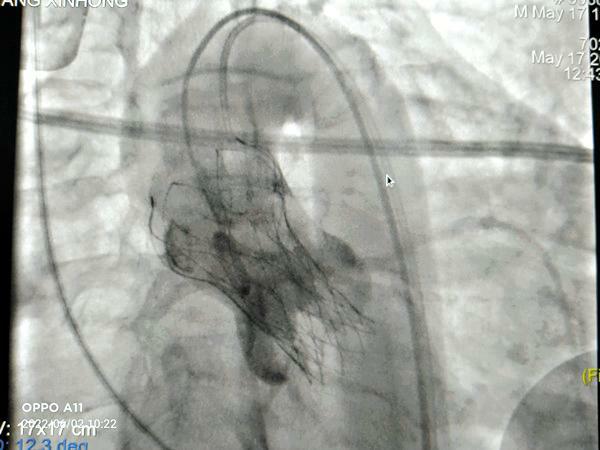

在我院心外科裴斐主任医师,麻醉科刘鹏斌主任医师、罗斌主治医师,超声科韩东刚副主任医师、金鑫主治医师,曹春晖护士长领导的护理团队等多学科协助下,韩振华主任、王新宏副主任医师、刘小军主治医师等先为患者行冠脉造影提示右冠近段95%狭窄(图1),先行PCI干预,右冠植入3.0x22mm支架1枚(图2)。后成功为患者植入TAV24mmVitaFlow瓣膜系统,DSA造影显示主动脉瓣位置良好,未见明显瓣周漏(图3),左右冠脉造影正常,术后即刻心脏超声示最大跨瓣流速129cm/s,最大跨瓣压差7mmHg(图4),顺利结束手术。